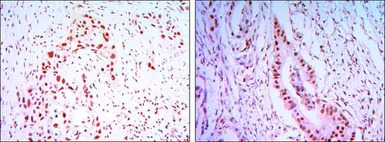

IHC-P analysis of lung cancer tissue (left) and colon cancer tissue (right) using GTX82818 CDC27 antibody [5C12].